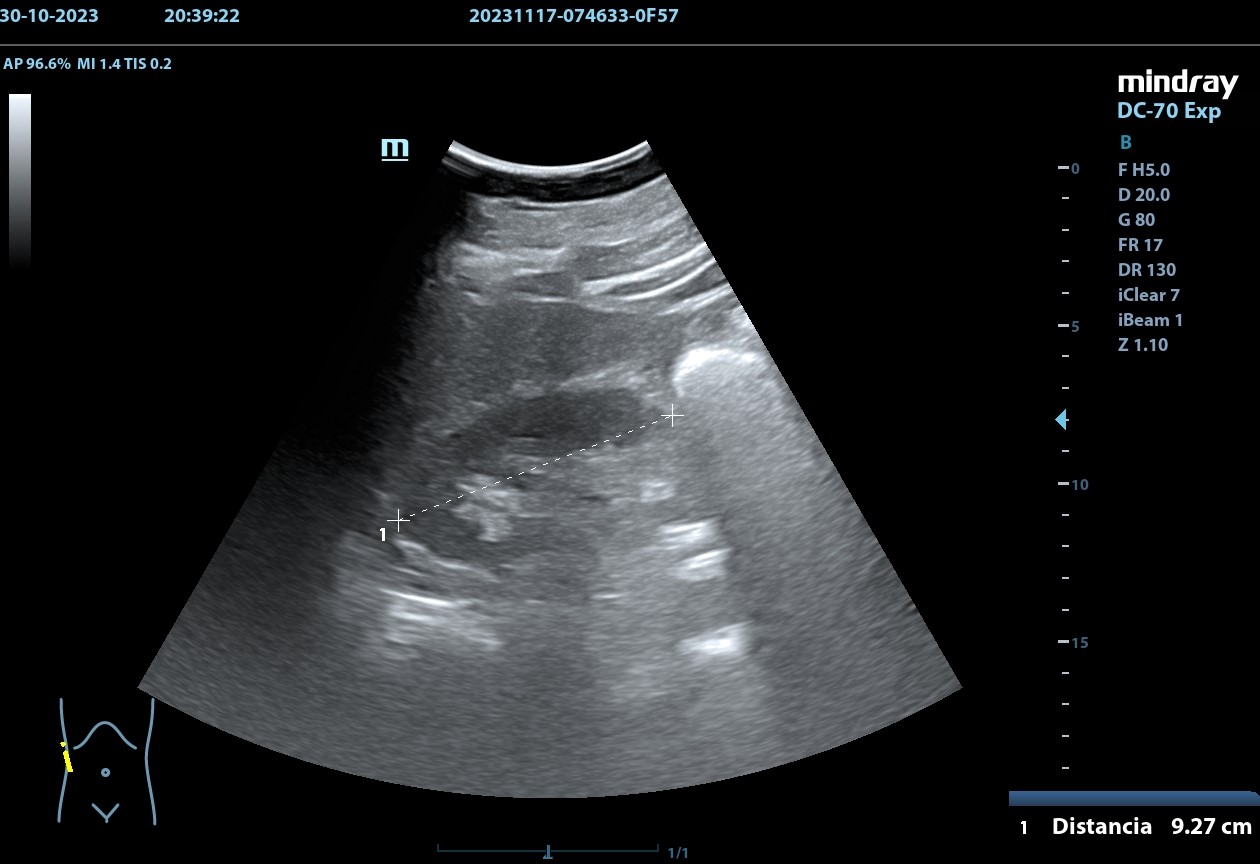

Hallazgos ecográficos

Se realiza, en consulta, una ecografía de las vías urinarias (POCUS), apreciando una lesión excrecente, pediculada, de 7,48 x 6,14 cm, que afecta a la pared izquierda y superior de la vejiga. Doppler negativo. No apreciándose jets ureterales. Riñón izquierdo de 11cm, y derecho de 9.27 cm, sin signos de dilatación de las pelvis renales que sugieran hidronefrosis.